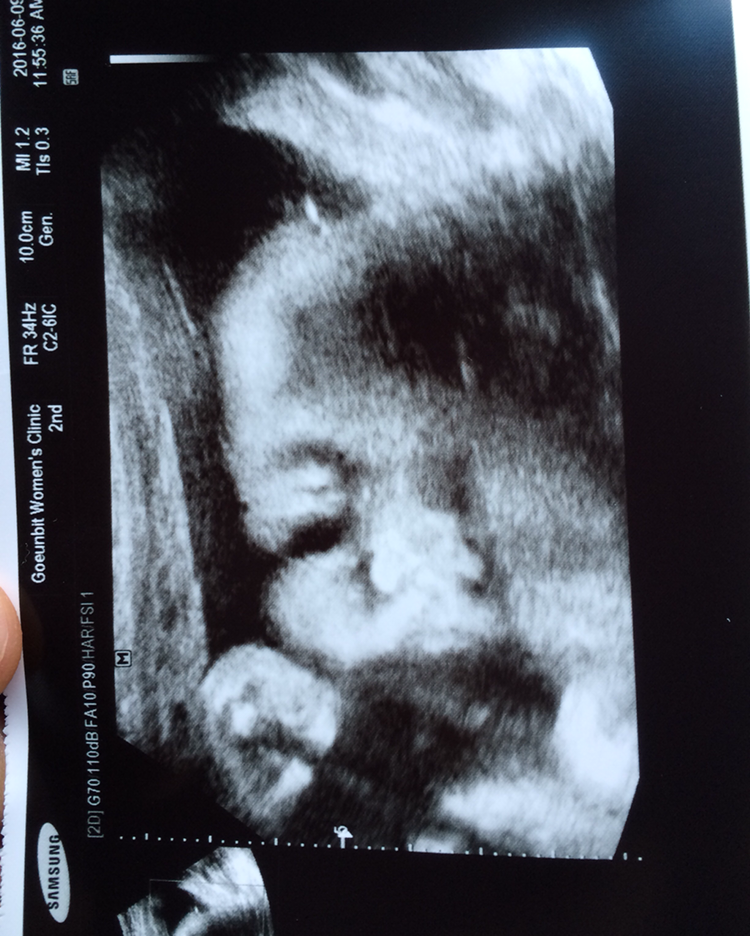

일단 대충 입고 병원에 도착하여 초음파를 검사했다. 그런데 아이는 한 달 전보다 볼에 살이 살짝 붙었긴 했지만 선생님께서는 주수보다 아이가 작다고 하셨다. 나의 체중은 8킬로나 늘었는데 아이의 체중은 고작 1.19킬로. 그렇다면 나머지는 그냥 다 내 살이었나 보다. 아기가 주수보다 크면 조산한다는 말을 들어서 평소에 먹고 싶었던 과일도 예전만큼 먹지 않았는데 아기가 작다고 하니 다 내 잘 못인 거 같아서 마음이 심란했다. 선생님께서는 괜찮다고 하셨지만 그래도 이제 아이를 위해 더 신경 써야 될 것 같다는 생각을 했다. 자극적인 음식은 최대한 줄이고 아이를 위해 이제 잘 먹어주려고 한다. 마음먹은 것처럼 잘 될진 모르겠지만 말이다.